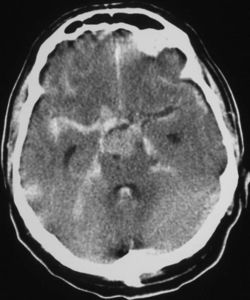

| CT scan of the brain showing subarachnoid hemorrhage as a white area in the center | |

يعتمد بصفة رئيسة على تصوير الدماغ، ومن أكثر طرق التصوير استعمالاً التصوير الطبقي المحوري (الشكل3)، وبدرجة أقل المرنان المغنطيسي. وجدير بالذكر أن تصوير الدماغ قد يخفق في إظهار النزف في نحو 5% من المرضى، وفي هذه الحالة يمكن اللجوء إلى استقصاء آخر هو البزل القطني للسائل الدماغي الشوكي. وتظهر دراسة السائل وجود أعداد كبيرة من الكريات الحمر، مما يثبت حدوث النزف.